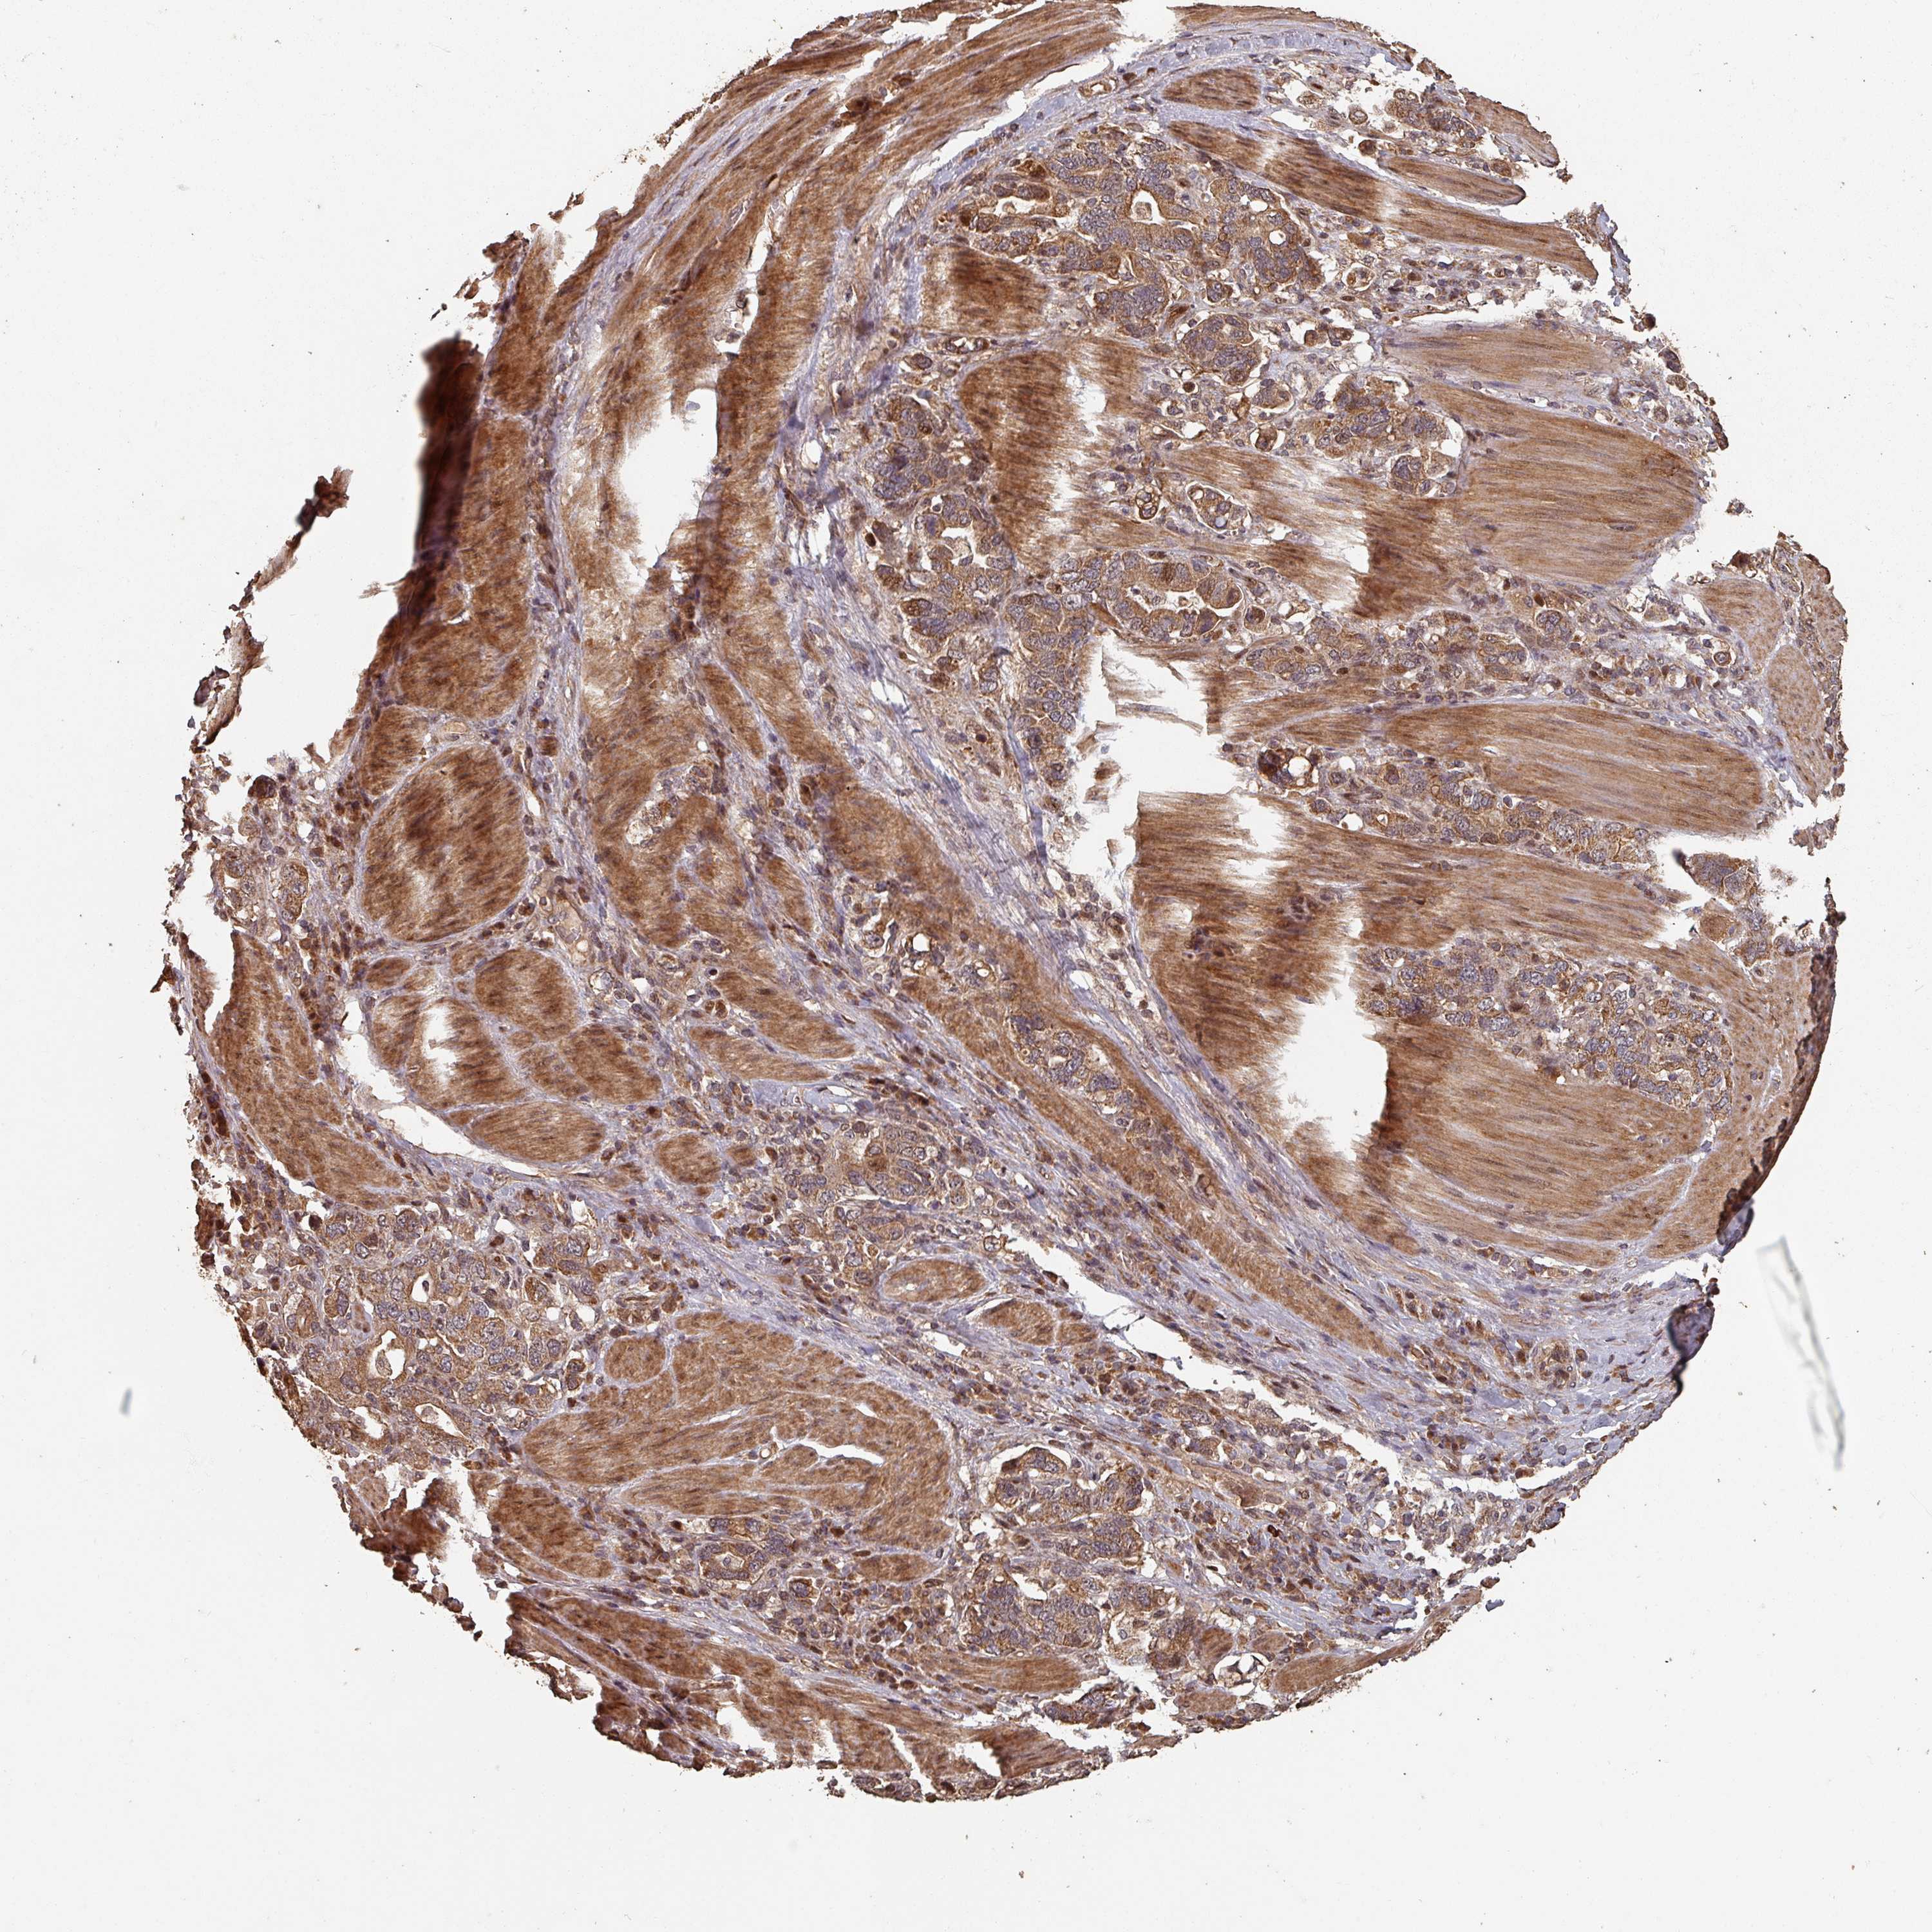

STOMACH CANCER - Protein expressioni

A mouse-over function shows sample information and annotation data. Click on an image to view it in a full screen mode. Samples can be filtered based on level of antibody staining by selecting one or several of the following categories: high, medium, low and not detected. The assay and annotation is described here.

Note that samples used for immunohistochemistry by the Human Protein Atlas do not correspond to samples in the TCGA dataset.

Antibody stainingi

Antibody staining in the annotated cell types in the current human tissue is reported as not detected, low, medium, or high, based on conventional immunohistochemistry profiling in selected tissues. This score is based on the combination of the staining intensity and fraction of stained cells.

Each image is clickable and will lead to virtual microscopy that enables deeper exploration of all samples and also displays staining intensity scores, fraction scores and subcellular localization as well as patient and tissue information for each sample.

Antibody HPA051122

Antibody HPA051123

Staining

High

Medium

Low

Not detected

Intensity

Strong

Moderate

Weak

Negative

Quantity

>75%

75%-25%

<25%

None

Location

Nuclear

Cytoplasmic/membranous

Cytoplasmic/membranous,nuclear

Adenocarcinoma, NOS